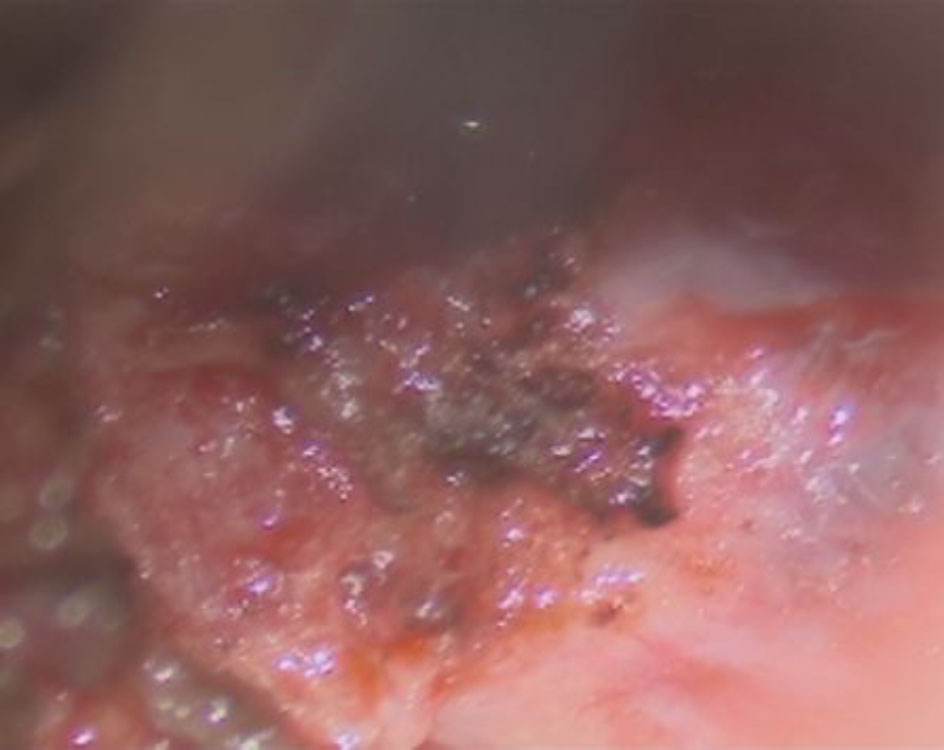

術中写真

No.’25_108 摘出 前

No.’25_108  摘出 中